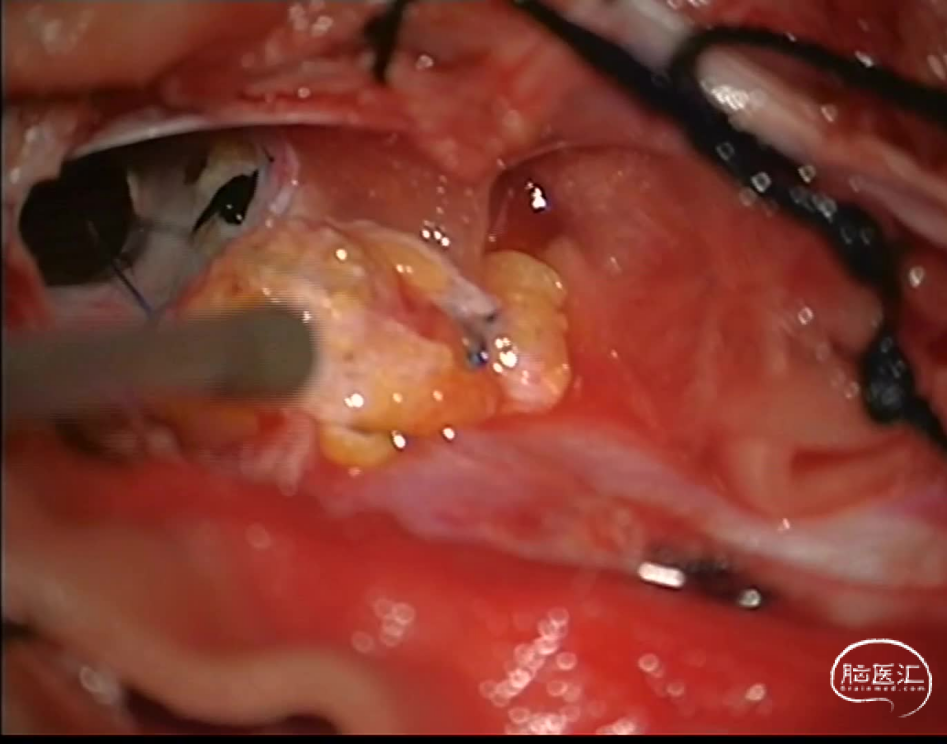

图2 手术过程: 病灶位于硬脊膜夹层见,见清亮脑脊液,有多个分隔,内镜下探查并开通数个分隔,漏口位于L1水平,以自体组织进行修补交通口。